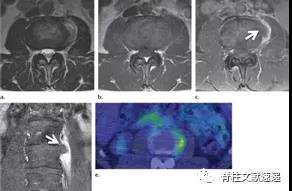

图注:背侧硬膜外椎间盘突出

图注:术前诊断倾向于硬膜外脓肿,术中见病灶呈致密纤维状,组织病理学检查显示纤维软骨盘伴反应性改变。